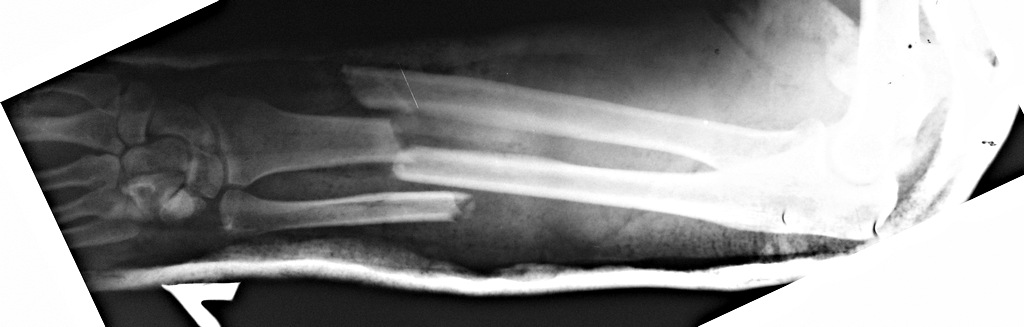

Вложение не в текстовом формате было извлечено&hellip;

Имя     : рис. 3.jpg

Тип     : image/jpeg

Размер  : 73471 байтов

Описание: отсутствует

Url     : http://weborto.net:8080/pipermail/ortho/attachments/20130302/71775e34/attachment-0007.jpg